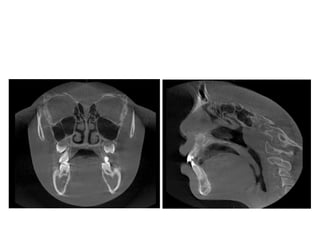

• 46.

• 62.

• 63.